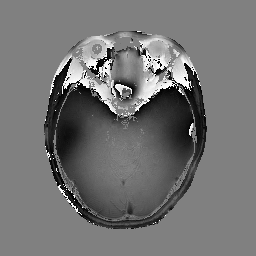

In the second set of evaluations, we considered regularization-based denoising of a 230180 single-channel T1-weighted MR image, obtained by applying complex coil-combination to an 8-channel dataset and subsequently adding simulated complex Gaussian noise. The ground truth and noisy images are shown in Fig. 3.

For reconstruction, the matrix was an identity matrix. Following Refs. [24, 10, 25, 28], the magnitude was regularized using a Huber-function penalty as given by Eq. (28), where a finite difference transformation was used to enforce spatial smoothness of the image. Following Ref. [10, 2, 4, 5, 7], the phase was regularized using a Tikhonov penalty as given by Eq. (29), also using a finite difference transformation to enforce spatial smoothness. All algorithms were initialized with the noisy image.